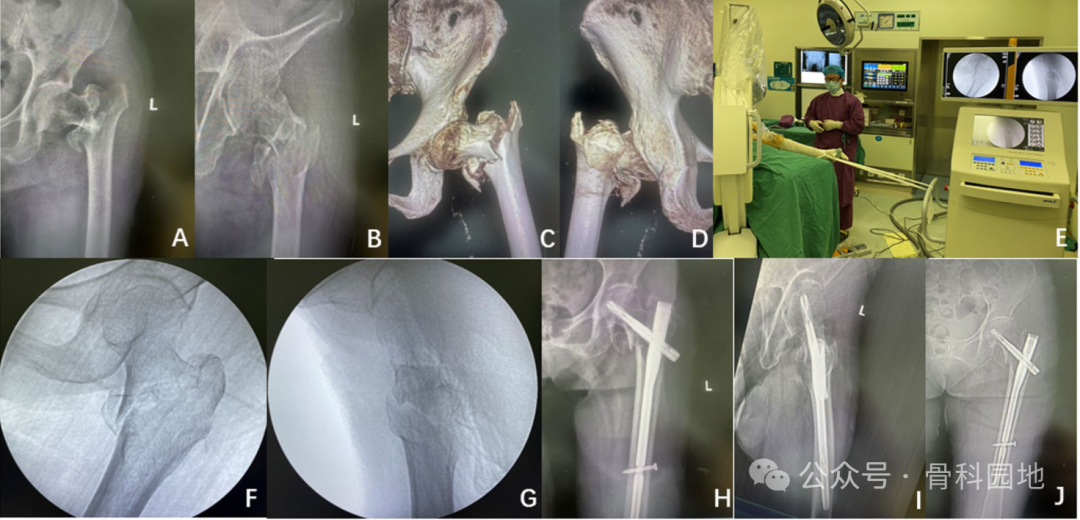

(A)常规牵引台和位于四肢之间的荧光透视装置

(B-C) C-Flex牵引装置:患者仰卧,10 °- 15° Trendelenburg倾斜,同侧髋关节抬高,踝关节固定在C形臂机器上;

(D-E)一个由外科医生控制的复位操作是在手术过程中在荧光镜的引导下从纵向牵引开始,并通过固定C形臂的四轮制动器来保持牵引